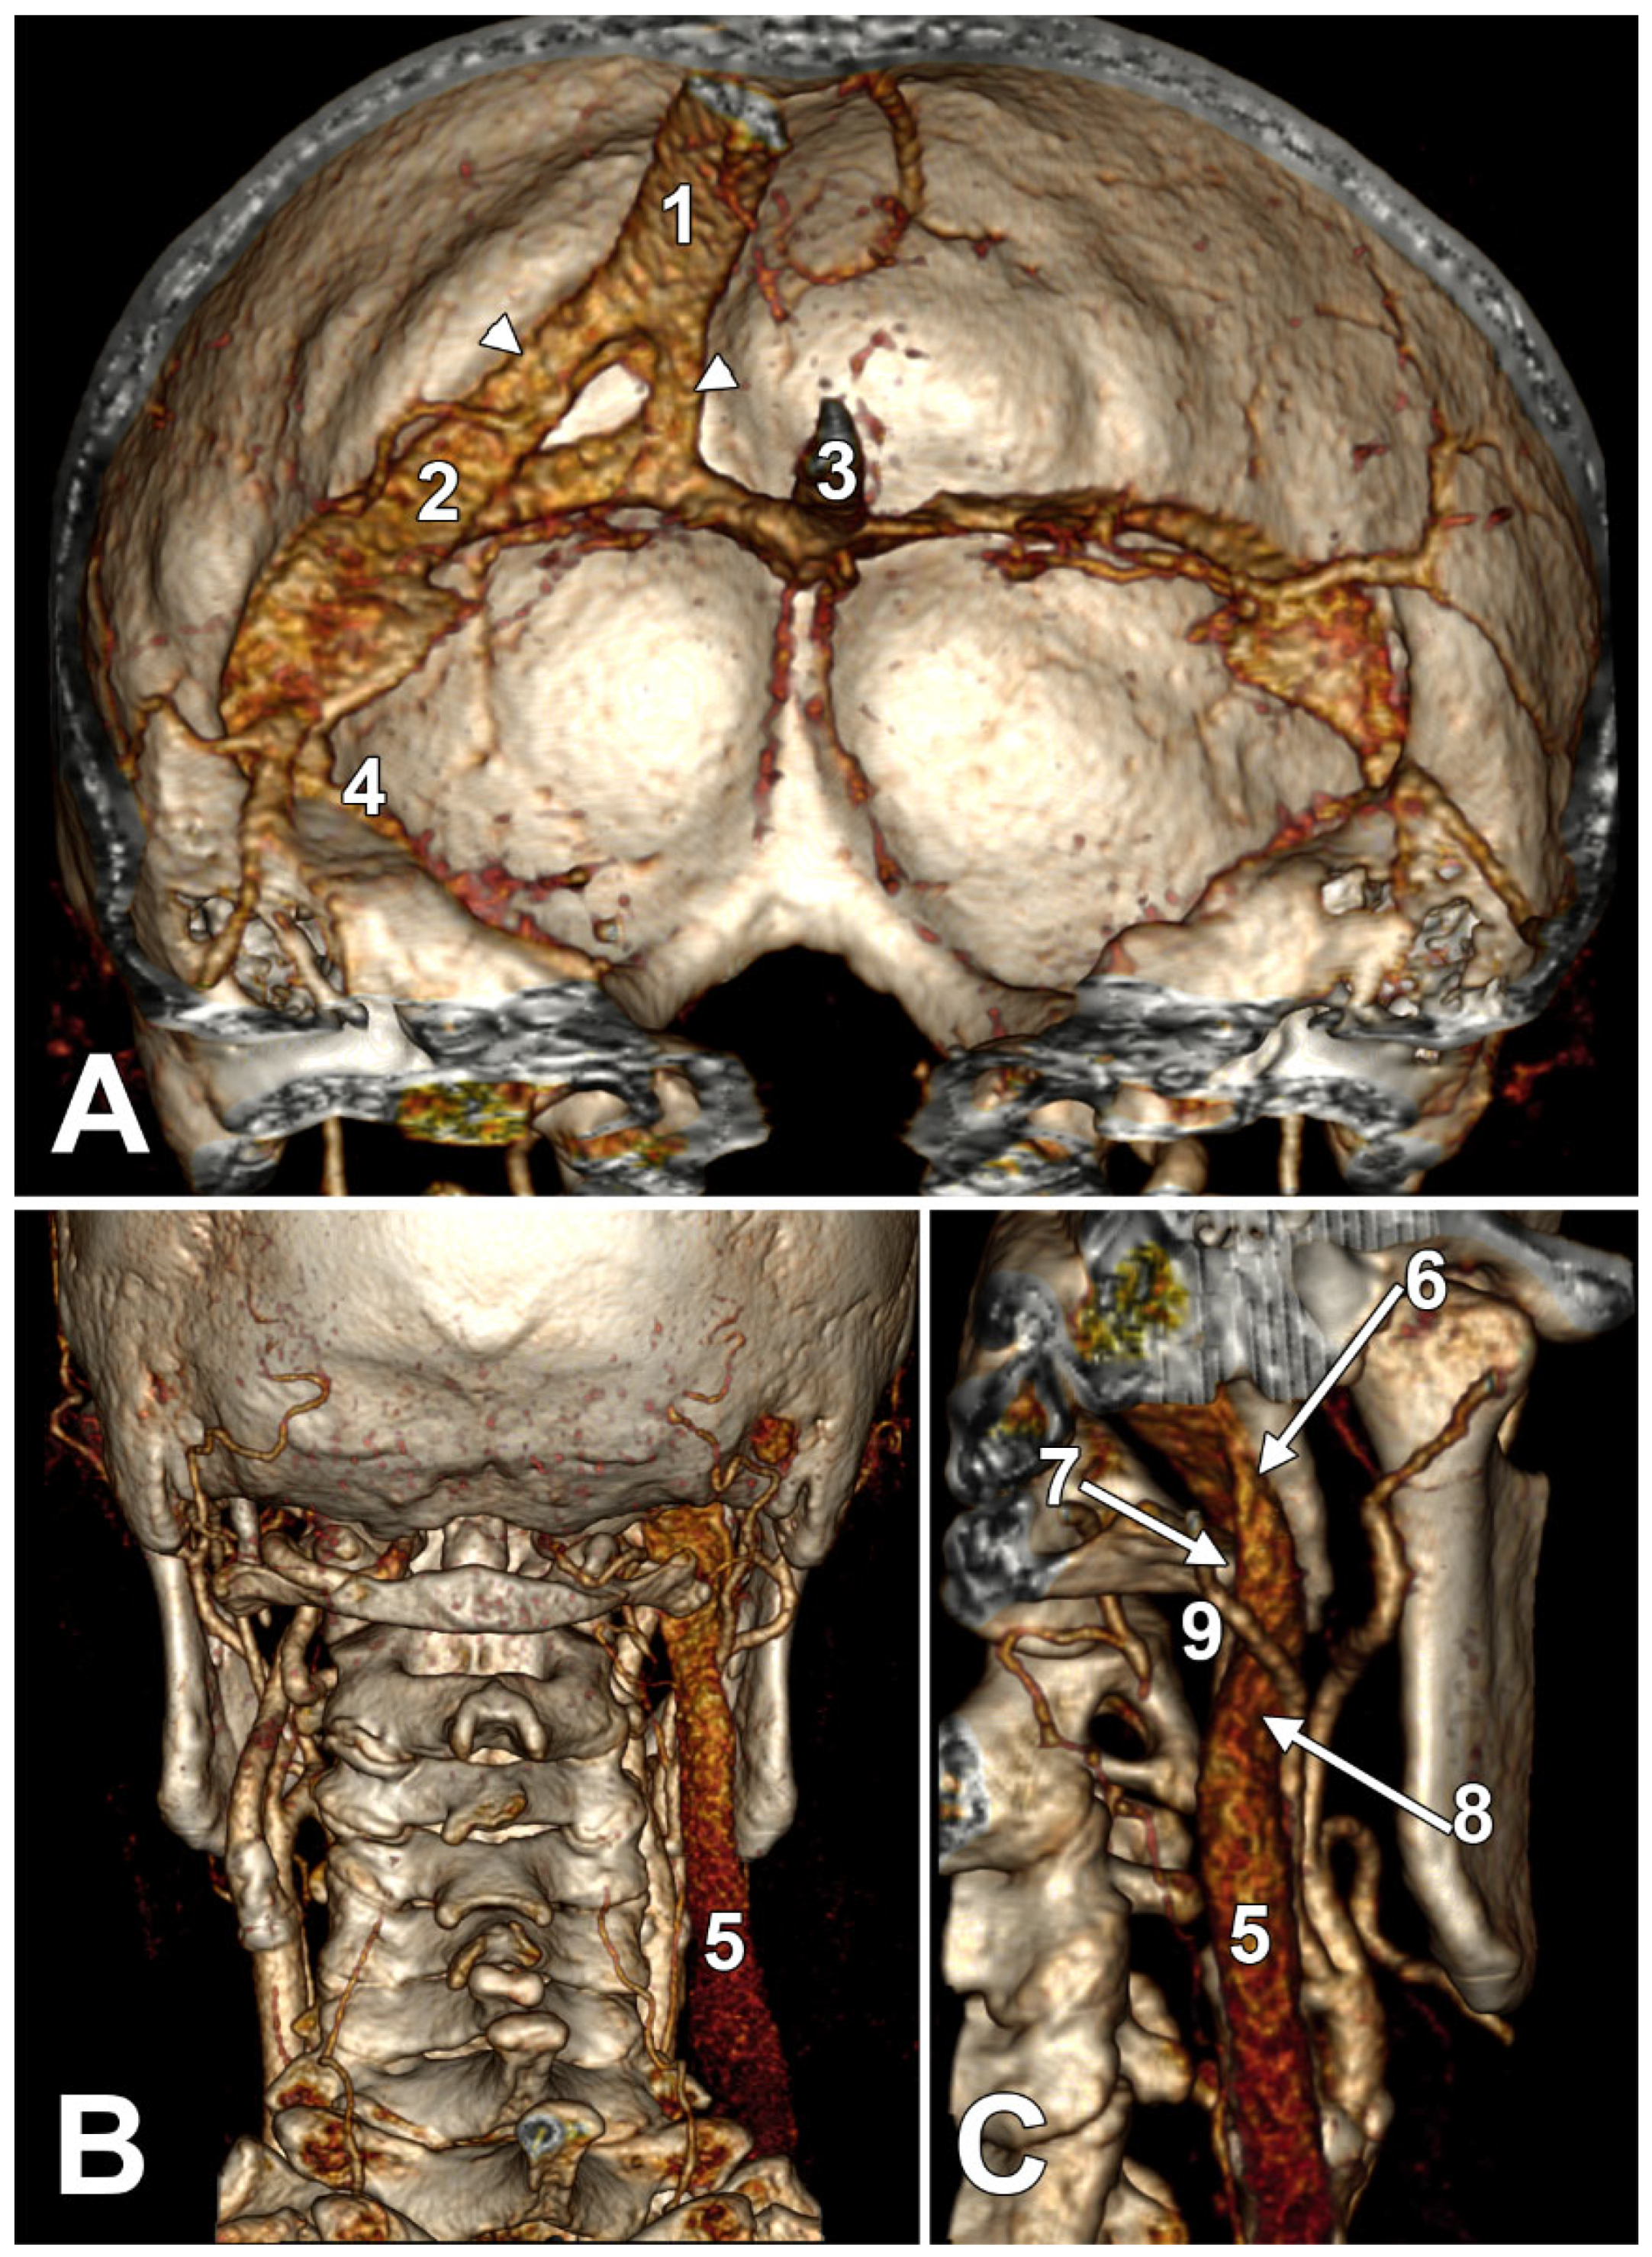

Patients are often asymptomatic due to compensatory enlargement of the contralateral IJV or collateral veins [85,86]. Enhanced drainage via the posterior neck veins or an increased flow through the external jugular veins may also compensate for the unilateral absence of the IJV. The drainage of intracranial blood from the side with an absent IJV could also be detoured via the transverse and sigmoid sinuses to the opposite side (Figure 4). Diagnosis is usually made via ultrasound, CT, or MRI, especially when the IJV cannot be visualised during central line placement [85,86,87,88]. Compensatory changes (e.g., enlargement of the opposite IJV) may mimic cervical masses [85,86,90].

We present here a case with bilateral long IPSs (Figure 7 and Figure 8). The novelty lies in the fact that both the long IPS and the IJV were pinched within the C1/SP nutcracker. This is because, on the one hand, the stenosis of the IJV determines different neurological deficits, discussed elsewhere in this paper, and, on the other hand, a compressed IPS could not be of use as an endovascular passage when it is compressed into a nutcracker. Specific documentation of IPS compression between the SP and atlas appears to be either very rare in the literature or potentially underreported. During an anatomical study of the archived angioCT file of a 63-year-old male case, bilateral long IPSs were found. The right one was 1.25 cm long, and the left one was 5.15 cm long. The right one had a diameter of 0.2 cm. The opposite one had a diameter of 0.32 cm. The right IPS was joined beneath the jugular foramen by the lateral condylar vein. The left IPS descended antero-medially to the left IJV. Both these veins were applied and compressed on the anterior side of the transverse process of the atlas. The two veins continued anterolaterally to the transverse process of the axis, and at 0.41 cm below that process, the IPS ended into the IJV. On both sides, the ICAs crossed anteriorly to the IPSs to enter the carotid canals. Therefore, the anatomic route of the IPS, the long IPS-to-IJV confluence site, and the diameter of the IPS are relevant in clinical procedures, such as cavernous sinus sampling, which requires catheterisation of both IPSs. Knowledge of the venous anatomy, including variants of the IPS and its branches, is crucial for the diagnosis and treatment of parasellar lesions.